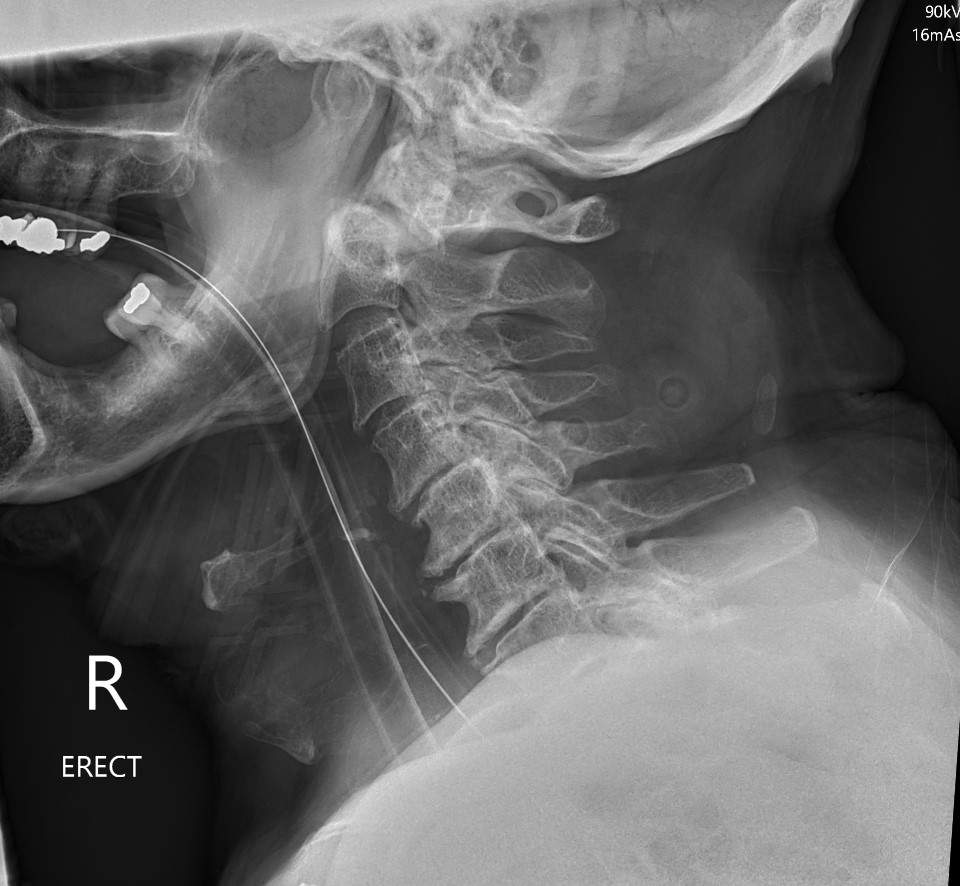

Neurological injury rare due to large cross sectional area of spinal canal

Dysphagia due to retropharyngeal hematoma

Myelopathy symptoms